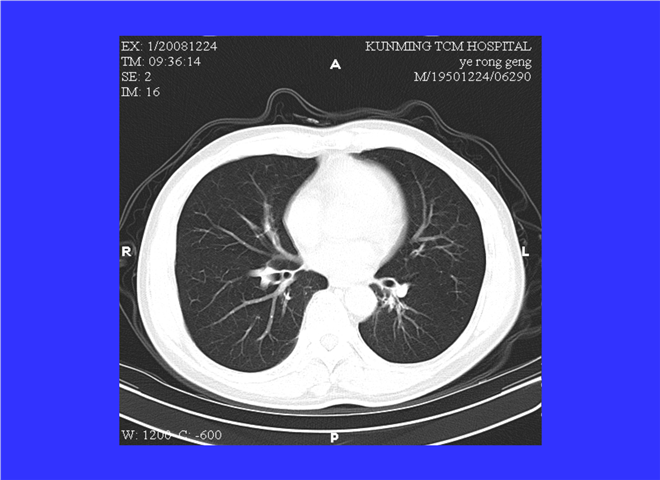

31_如何阅读胸部CT片